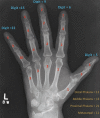

Objective Enchondromas are benign tumours of hyaline cartilage most frequently arising in the bones of the hand and the optimum surgical management strategy for these is debated. We present an audit of the surgical management of 57 enchondromas referred to our tertiary hand surgery department over a period of 12 years (2008-2020) and describe our surgical technique for this procedure as well as a comparison with other studies in the literature. Materials and Methods Retrospective audit of our practice. Data were extracted from our institutional operative database to identify all patients undergoing surgical management of enchondromas during the time period. The individual electronic patient records were then evaluated to extract demographics and outcome data. Results Our results demonstrate excellent clearance of enchondroma (74% Tordai group 1 radiological resolution) with very low complication rates and no recurrence. Our results also emphasize the importance of surgical management of enchondromas to allow diagnosis of rare chondrosarcoma (3.5% in this study). Conclusion A larger randomized controlled trial is still required to adequately determine the differences between the surgical options available and determine the best possible surgical approach to these cases. Level of evidence is III.